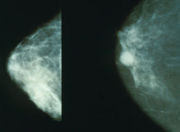

| Normal (left) versus cancerous (right) mammography image |